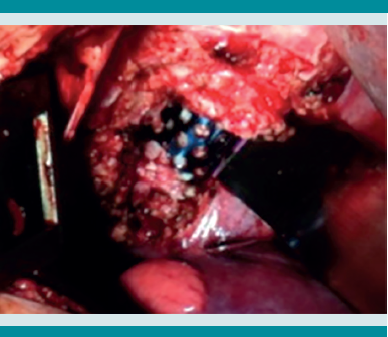

En la sesión multidisciplinaria hospitalaria se decidió que la mejor opción sería el tratamiento quirúrgico radical, que incluyó: toracotomía anterior, corporectomía (T7-T8), resección y toma de cultivo de granuloma (Figura 8), aplicación de una malla de titanio con injerto autólogo y matriz ósea (Figura 9), instrumentación posterior con barra de Luque y alambrado sublaminar de T4 a T11 (Figura 10 a-b), que se llevó a cabo sin complicaciones transoperatorias, posoperatorias inmediatas ni mediatas.